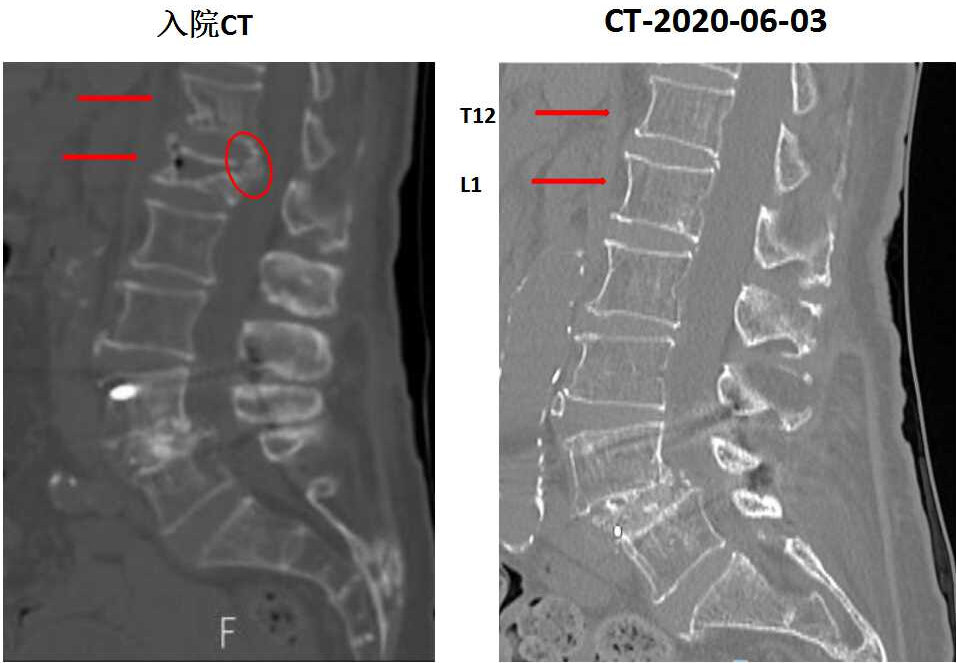

陈奶奶骨折前后CT结果对比,箭头示本次入院骨折椎体,圆圈示骨折压迫脊髓

陈奶奶骨折后CT结果,示骨折压迫脊髓

看这个MRI和CT的结果,T12和L1这两个地方的压缩性骨折肯定没跑了,但是这个骨折有一小部分压迫到了脊髓和神经,失去了打骨水泥这种微创手术的机会。不得不做了一个大的开放性的后路T12、L1椎体骨折切开复位内固定术。又给加了5对也就是10个钉子在里面。